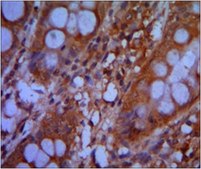

Immunohistochemistry Analysis: A 1:200-1,000 dilution from a representative lot detected CHD3 in colon cancer tissue.

Detect CHD-3 using this mouse monoclonal antibody, Anti-CHD3 Antibody, clone 2G4 validated for use in western blotting, IHC, Immunofluorescence & Flow Cytometry.